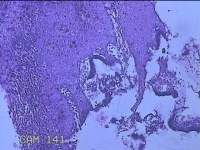

宫颈3点、9点、11点、12点组织

性别

女

年龄

37岁

临床诊断

人乳头瘤病毒感染

一般病史

HPV其他12型阳性

标本名称

大体所见

1.“宫颈3点组织”:灰白粉红色组织1x0.8x0.2cm一块。 2.“宫颈9点组织”:灰白粉红色组织0.7x0.5x0.2cm一块。 3.“宫颈11点组织”:灰白粉红色组织0.8x0.5x0.2cm一块。 4.“宫颈12点组织”:灰白粉红色组织8.5x0.5x0.2cm一块。

图2